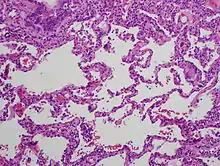

The acute form can be characterized by poorly formed noncaseating interstitial granulomas and mononuclear cell infiltration in a peribronchial distribution with prominent giant cells.[1] The subacute, or intermittent, form produces more well-formed noncaseating granulomas, bronchiolitis with or without organizing pneumonia, and interstitial fibrosis.[1] Much like the pathogenesis of idiopathic pulmonary fibrosis (IPF), chronic HP is related to increased expression of Fas antigen and Fas ligand, leading to increased epithelial apoptosis activation in the alveoli.[21] Cholesterol clefts or asteroid bodies are present within or outside granulomas.[1]

Lung biopsy

Lung biopsies can be diagnostic in cases of chronic hypersensitivity pneumonitis, or may help to suggest the diagnosis and trigger or intensify the search for an allergen. The main feature of chronic hypersensitivity pneumonitis on lung biopsies is expansion of the interstitium by lymphocytes accompanied by an occasional multinucleated giant cell or loose granuloma.[7][22]